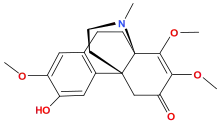

Morphinones and morphols

- 14-Cinnamoyloxycodeinone

- 14-Ethoxymetopon

- 14-Methoxymetopon

- 14-Phenylpropoxymetopon

- 3-Acetyloxymorphone

- 3,14-Diacetyloxymorphone

- 7-Spiroindanyloxymorphone

- 8,14-Dihydroxydihydromorphinone

- Acetylcodone

- Acetylmorphone

- α-hydrocodol (=dihydrocodeine, )

- Benzhydrocodone

- Bromoisopropropyldihydromorphinone cas?

- Codeinone

- Codoxime

- Conorfone (codorphone)

- IBNtxA

- Thebacon (acetyldihydrocodeinone, dihydrocodeinone enol acetate)

- Hydrocodone

- Hydromorphone

- Hydroxycodeine

- Metopon (=methyldihydromorphinone)

- Morphenol

- Morphinone

- Morphol

- N-Phenethyl-14-ethoxymetopon

- Noroxymorphone

- Oxycodone

- Oxymorphol

- Oxymorphone

- Pentamorphone

- Semorphone

Structures

| Morphinones and morphols | ||||